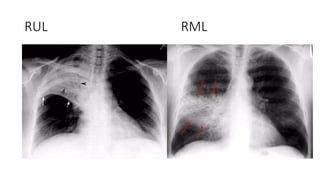

RUL RML

RUL Bronchopneumonia